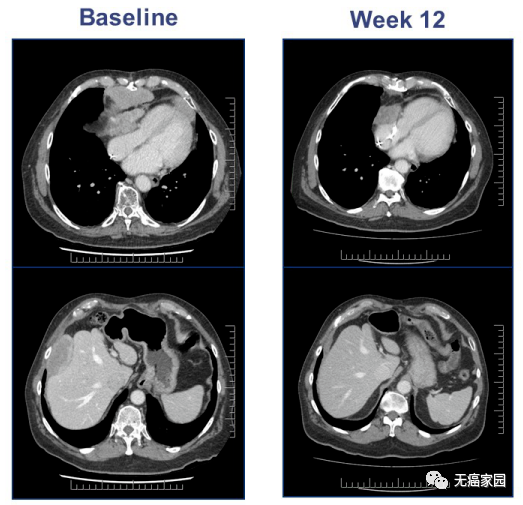

一名67岁的老年男性,有4年的滑膜肉瘤患病史,心包复发,既往采用减瘤术和异环磷酰胺治疗,MAGE-A4高表达。输了9.95*109的TCT细胞产品。基线扫描显示很高的疾病负担155mm,疾病在心包和肝脏。输液后扫描,在第12周时,靶向的肿瘤病灶大程度减少了45%。骨髓异常综合征方面在一段时间后继续减少了71%,由于新的不明靶向的病灶的出现,在第24周时发生了疾病进展。